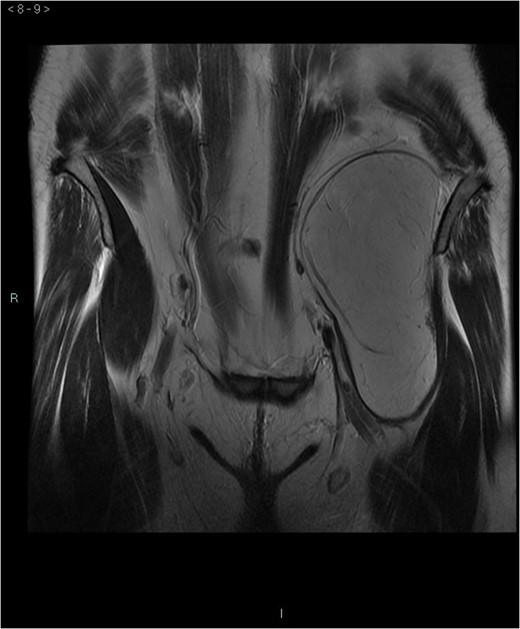

Abdominal hibernoma is a rare slow-growing tumor originating from brown adipose tissue. Due to its rarity, only a few case reports have been published so far. Pelvic localization is anedoctal and preoperative differential diagnosis with other malignancies may be challenging. We present the case of a woman who, due to a lower abdominal pain, underwent an abdominal ultrasonography with diagnosis of a 15 cm hyperechogenous pelvic mass. A subsequent MRI showed a 16 × 5.8 × 7.8 cm3 lesion anterior to the left iliacus muscle, with an intra- and extrapelvic component longitudinally extending from the left anterior superior iliac spine until the lesser trochanter. Surgical resection was performed and final histopathology was consistent with hibernoma. This report emphasizes the necessity to include hibernoma among differential diagnosis when a retroperitoneal abdominal mass is diagnosed and the difficulty to perform preoperatively this diagnosis due to the extreme rarity of these neoplasms.

A 58-year-old woman was evaluated for lower abdominal pain, without additional symptoms. An abdominal ultrasonography revealed the presence of a 15 cm homogenous mass, located in the left pelvic cavity. Subsequent MRI showed a capsulated mass, isointense with the adipose tissue, longitudinally extending from the left inguinal area to the left leg root and located on the medial aspect of the left iliac bone. MRI also revealed within the mass some fibrotic branches containing small blood vessels. No evidence of extracapsular invasion of the surrounding structures was evident (Figs 1–6).

Preoperative differential diagnosis is mainly based on radiologic imaging and is very difficult, because no pathognomonic signs exists for diagnosis of hibernoma; usually CT-scan shows an homogenous lesion, whose density is between subcutaneous fat and skeletal muscle; MRI shows slightly lower signal intensity on T1 weighted spin-echo (T1WSE), marked enhancement and partial fat suppression on short Tau inversion recovery (STIR) and fat-saturated sequences [5].